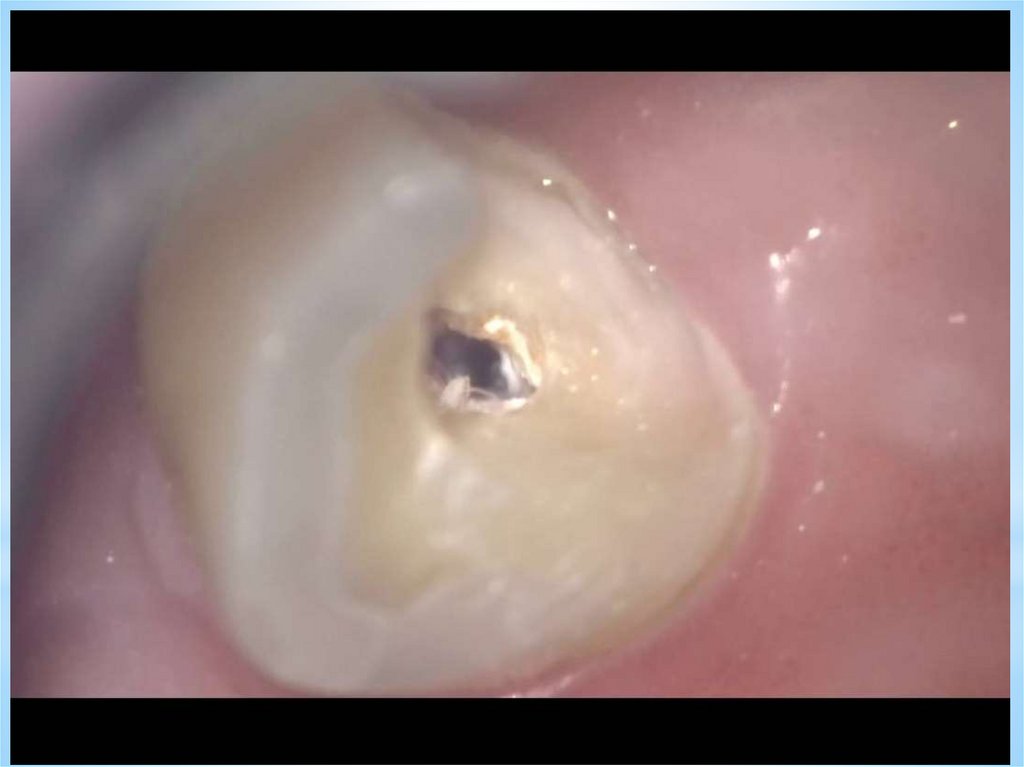

4.

• 0,6 увеличение

5.

• 1 увеличение

6.

• 2,4 увеличение